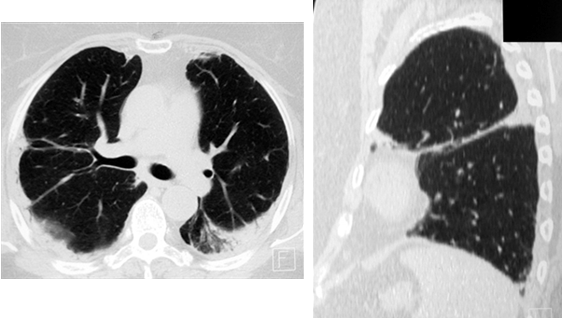

Довольно часто при саркоидозе в процесс вовлекается плевра, в виде её утолщения от нерезко выраженного до массивного, иногда с элементами обызвествления (рис. 7).

Рис. 7. РК-томограммы пациентки Ф., 59 лет. Определяются участки уплотнения лёгочной ткани субплевральной локализации с вовлечением в процесс костальной и междолевой плевры